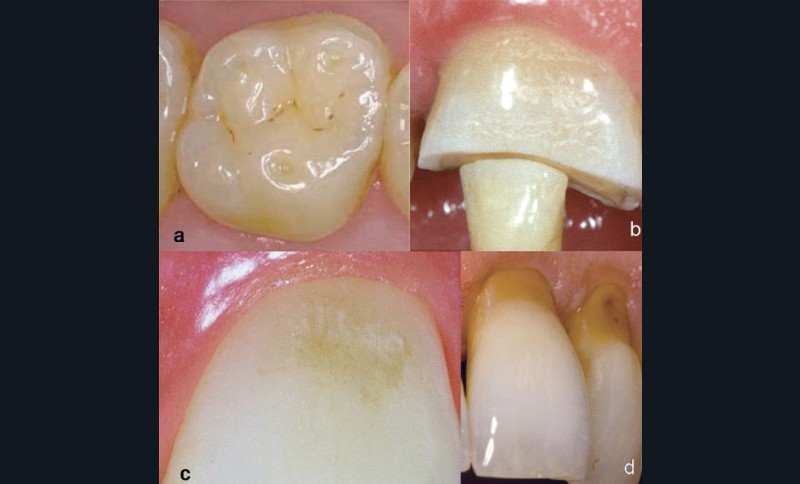

Les lésions érosives présentent des contours progressifs. L’émail sus-jacent est d’aspect mat ou satiné en raison du léger mordançage qu’il a subi. Lorsque les dents ont déjà été restaurées, l’obturation dentaire semble émerger en surcontour par rapport aux surfaces dentaires(fig. 2), car le matériau dont elle est constituée (hormis les ciments aux verres ionomères) n’est pas sensible à l’attaque acide. Cet élément est par ailleurs déterminant lors de l’établissement du diagnostic différentiel.

Plusieurs modes d’usure dentaire, dont l’érosion, peuvent être synchrones et interagir les uns avec les autres, ce qui rend le diagnostic clinique des érosions dentaires d’autant plus difficile(fig. 3 et 4).